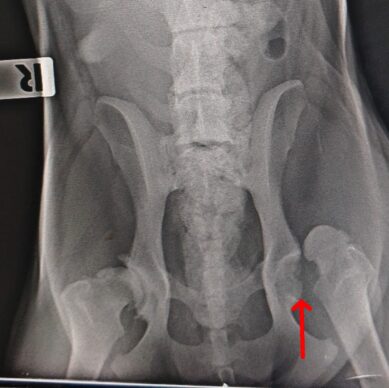

köpek